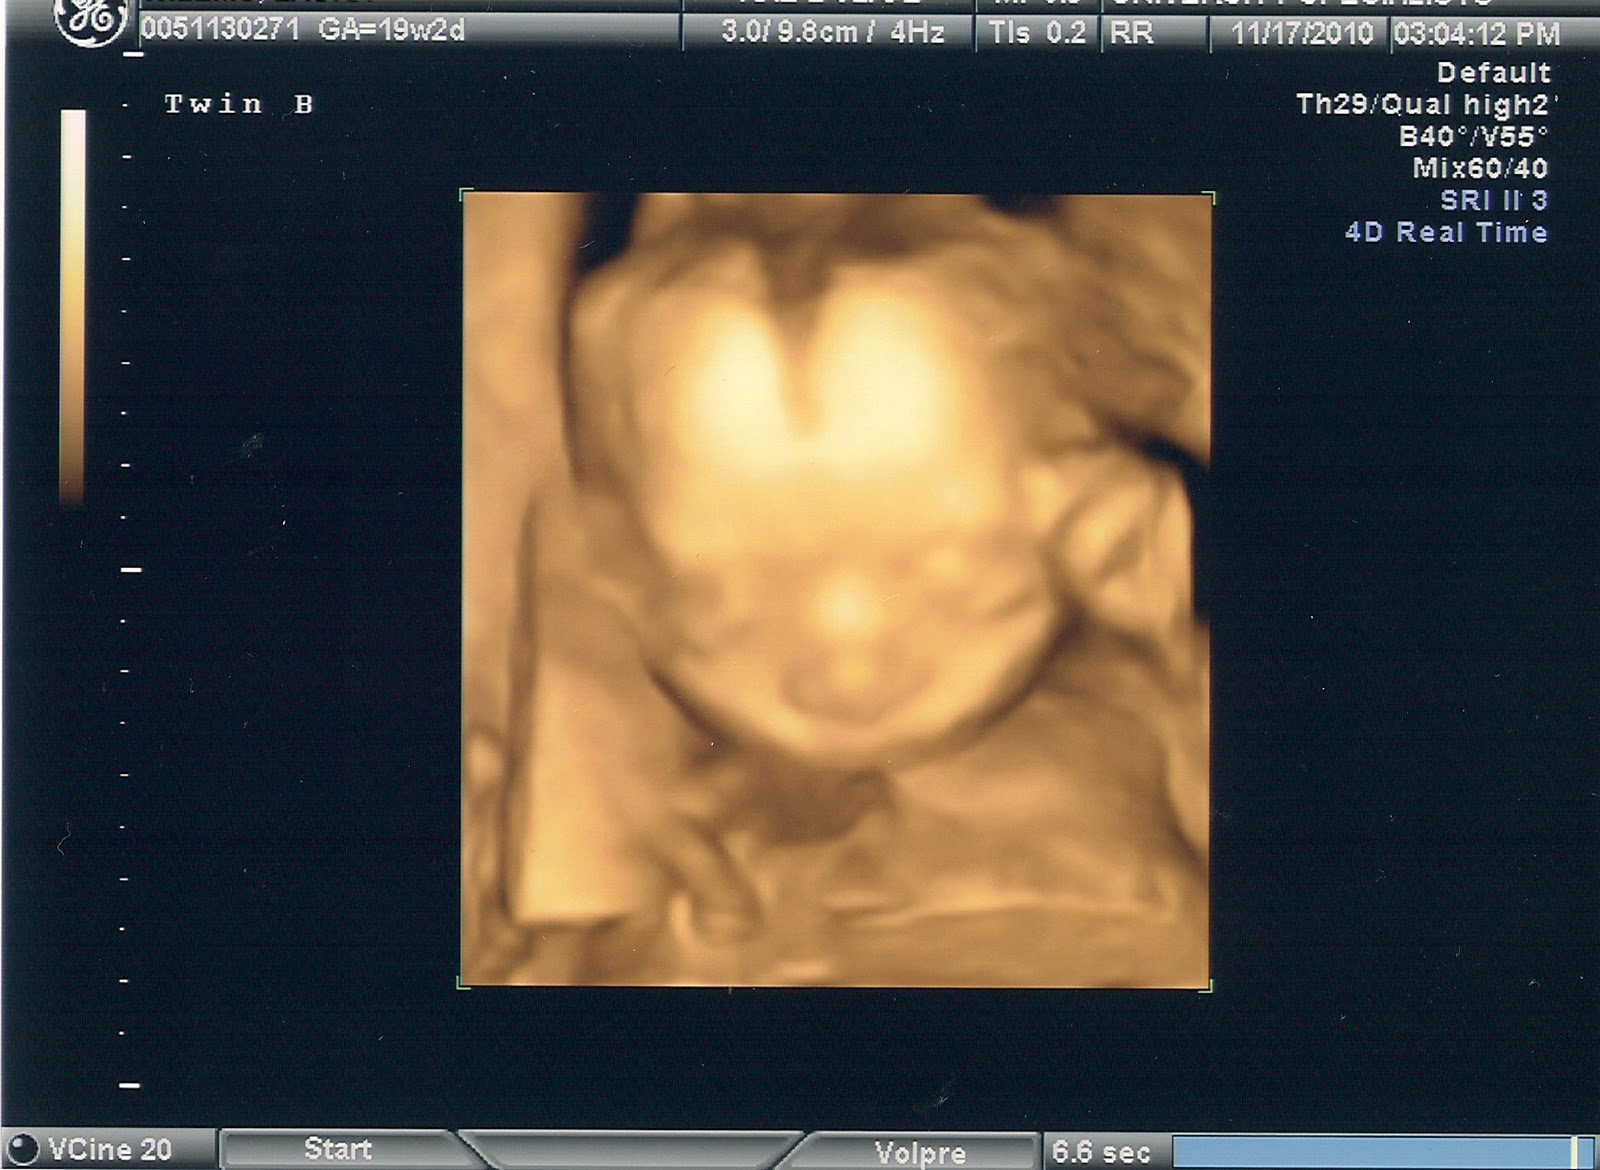

From babypulver.blogspot.com

Baby Pulver!!! 19 week Level 2 Ultrasound Level 2 Ultrasound Charges the cost of level 2 ultrasound ranges between 1000 to 3650 inr. a level ii ultrasound resembles a transabdominal ultrasound and should not be confused with a transvaginal ultrasound. an anomaly scan, also called tiffa scan or ultrasound level ii scan checks for any anomalies in your baby's organs at around 20 weeks of. However, the price. Level 2 Ultrasound Charges.